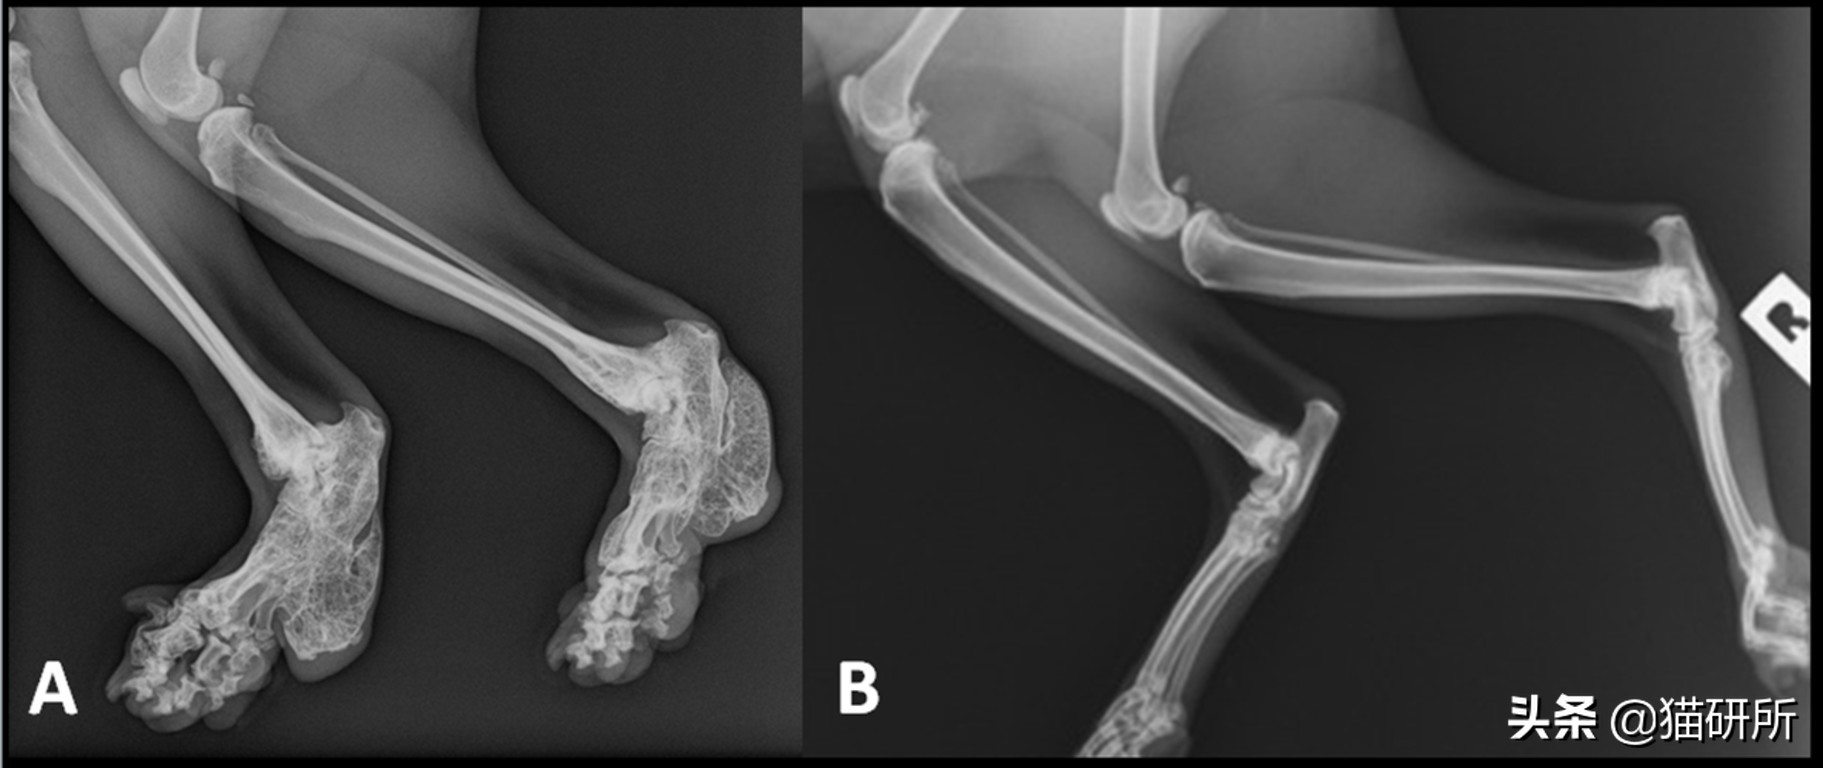

如短头品种综合征和折耳猫软骨发育不良,都是因为呈现这个特点的基因,本身就是一个发病基因。

折耳的背后,是软骨发育不良。图自gulfnews/theconversation.com